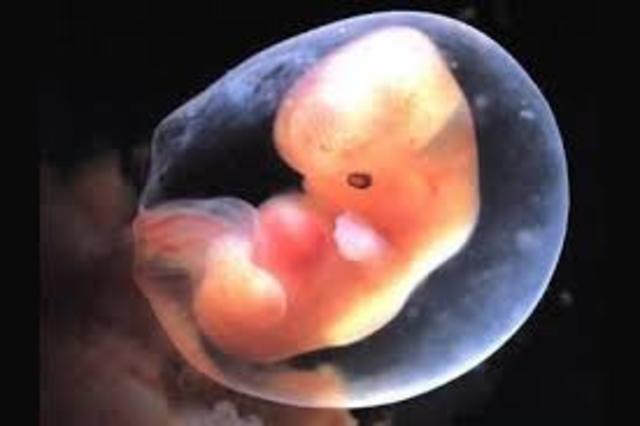

El embarazo se mide en semanas a partir de la última regla, pero el bebé se concibe antes. A partir de la semana 2 del embarazo, se desarrolla lo que llamamos embrión, que tiene básicamente una cabeza, un tronco y una cola rizada. Las primeras semanas de embarazo son muy importantes porque, aunque todavía es un embrión, empieza a desarrollar los cimientos de lo que serán sus órganos, sus rasgos y su sistema nervioso.

• semana 3 de embarazo

semana 3 de embarazo

Los primeros órganos empiezan a formarse. Las maravillosas células del corazón

Con solo 3 semanas de embarazo, el corazón es un grupo de células musculares aletargadas y diminutas, pero que sobre los 22 días explota de vida. Una célula se contrae espontáneamente, contagia a sus vecinas y comienza una reacción en cadena hasta que todas las células del corazón empiezan a latir.

El embrión en la semana 4 de embarazo tiene el tamaño aproximado de una judía y crece un milímetro al día. Sus ojos empiezan a distinguirse como dos puntos negros. empiezan a desarrollarse los bultitos que formarán más tarde sus brazos y piernas. Además, en la cuarta semana ya habrá capas de tejido que formarán el rostro de tu bebé. Su diminuto corazón, formado ahora por una única cámara, va más rápido